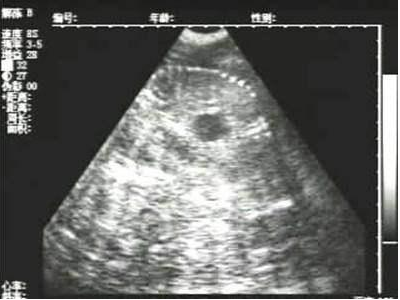

母豬B超檢測空懷圖片

獸用B超機檢測母豬空懷圖像